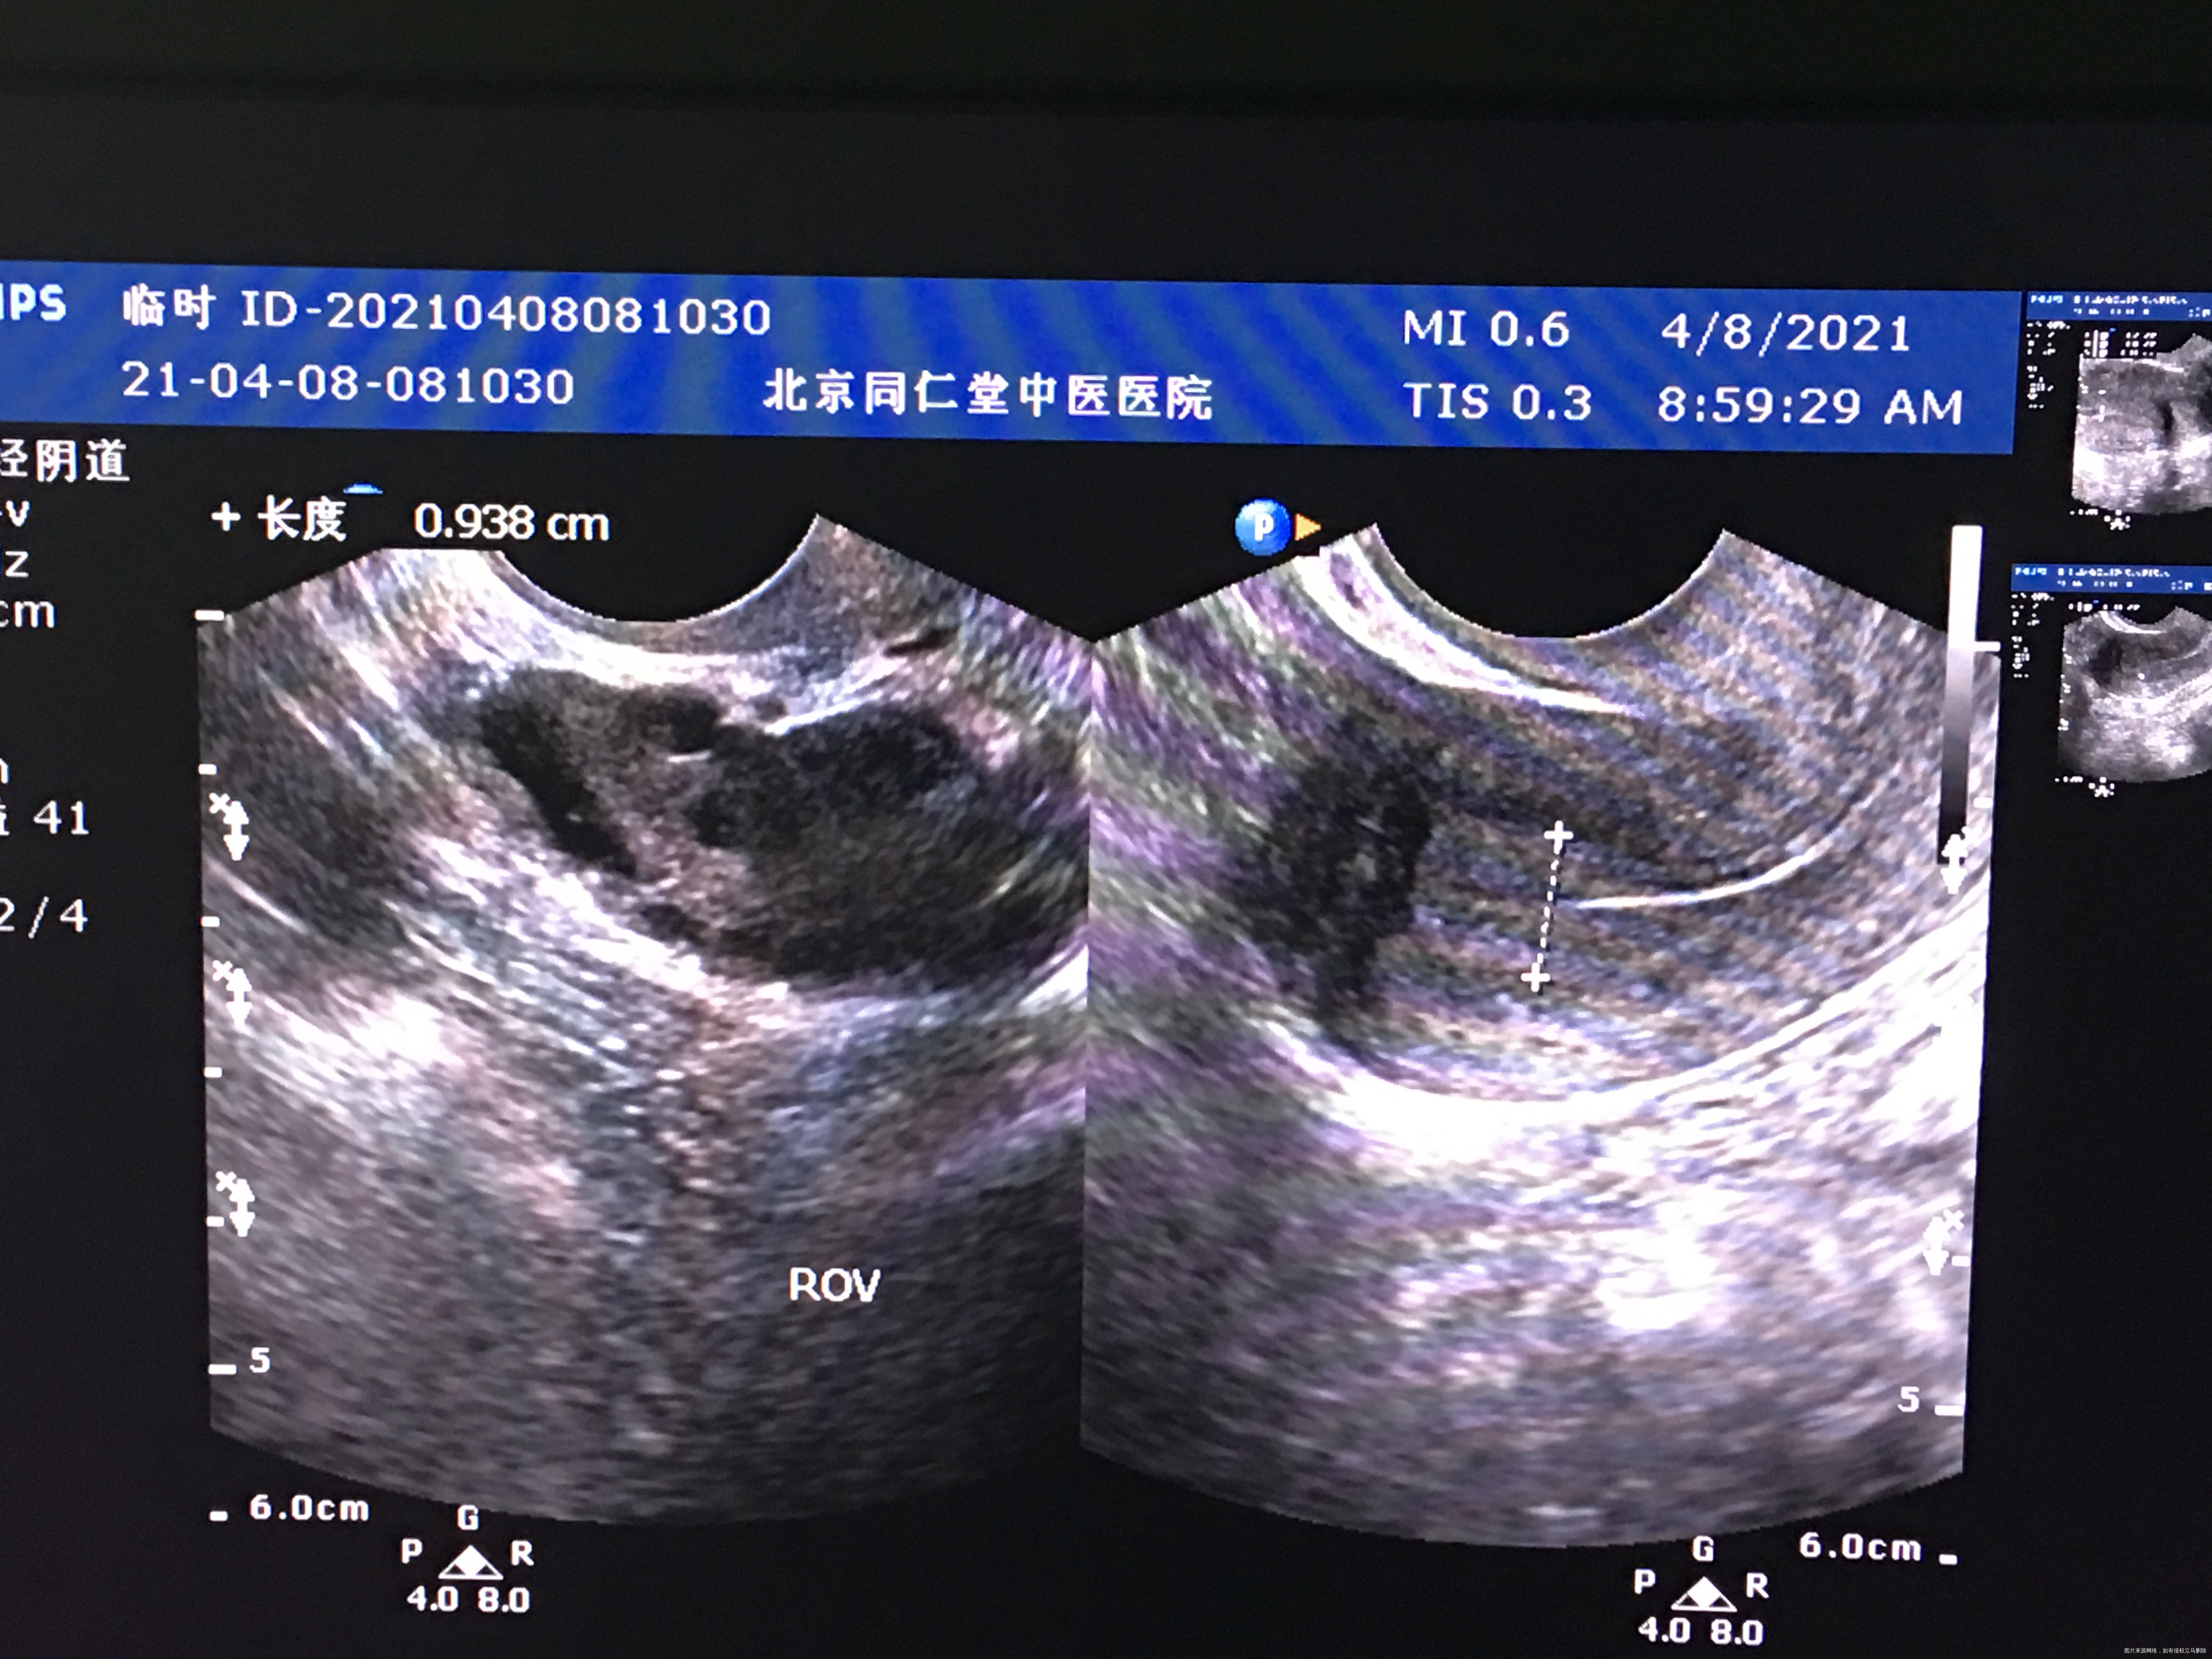

您好,我月经不规律,上次月经3.月2日,请问我现在这个b超显示已经排卵了吗?现在内膜是0.93

你好,根据这个B超没看出来是否已排卵,我只看到卵泡比较多,你应该是有点多囊卵巢,建议医院就诊全面评估治疗!

你好!内膜厚度可以,没有排卵迹象。继续检测卵泡看看。

排卵期内膜厚正常,和卵泡发育不一定同步。成熟大卵泡,排卵后会有一些特征,比如宫腔有少量积液,卵泡膜张力变化等,你的情况不明显,明天再做b超,比较下。

根据B超看不出是否已排卵,排卵后形成黄体,但是很多医院不报告黄体,内膜厚度可以,你可以测个血孕酮值看看,孕酮值大于5考虑已排卵。